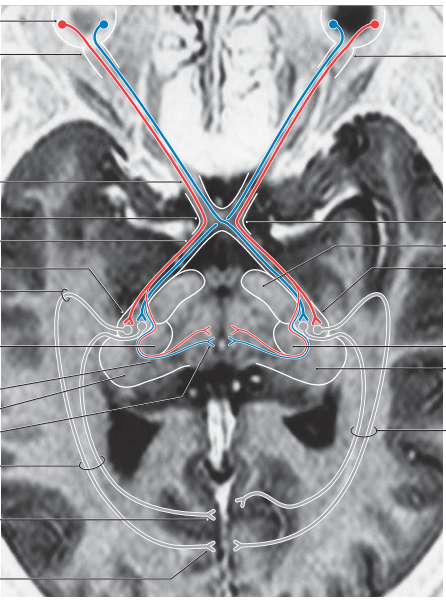

describe the pupillary light reflex circuitry

• shining light into the right eye activates retinal ganglion cells

• the axons of retinal gang. cells form the afferent limb of the reflex arc

• about 50% of the fibers forming the optic nerve stay ipsilateral and continue in the optic tract of the same side, while the other 50% gang. cell axons cross at the optic chiasm and then run along the contralateral optic tract

• not all fibers carrying visual info. synpase in the LGN; some fibers synapse in the pretectal nucleus of the midbrain

• collaterals of axons originating in the pretectal nucleus bilaterally innervate the EW nuclei, which are the accessory nuclei of CN III